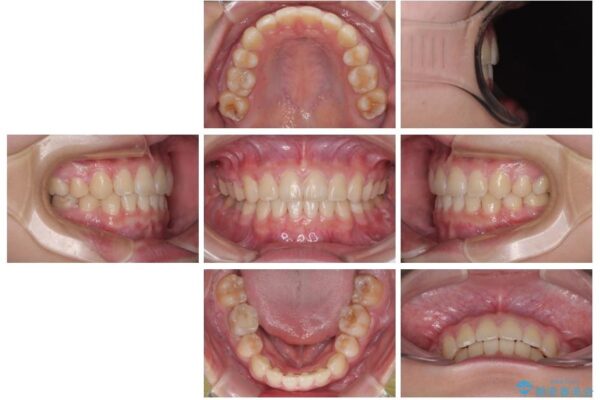

治療後

• 転勤でも安心して治療継続 抜歯スペース閉鎖と深い噛み合わせ改善のワイヤー矯正 治療後画像

結果的に1年半で、再度転勤になる前に治療を終えることができました。